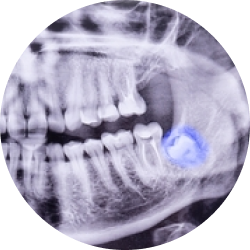

Больной осуществляет полное диагностическое обследование. Необходимо пройти рентгеновский снимок конкретного зуба и ортопантомограмму, сделать трехмерные изображения с помощью компьютерной томографии. При необходимости назначаются различные анализы, прием других врачей. Стоматолог изучает полученную информацию. Он ставит диагноз, выбирает методику экстракции зуба, освещает ориентировочную стоимость услуг, рассказывает о рисках хирургического вмешательства.